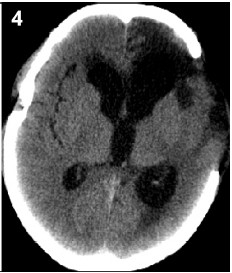

2 Complications secondary to DC 2.1 Brain herniation through the craniectomy defectThis complication may have several different diagnostic criteria. In our study,we defined it as the herniated brain tissue more than 1.5 cm above the plane of the cranial defect[2]. Brain herniation through the craniectomy defect is much more frequent when a limited surgical decompression was performed (Figure 1),such as circular compression and subtemporal compression[4]. By removing part of the skull,DC tries to prevent herniation and to reconstruct cerebral blood perfusion to improve patients’ outcomes. The decompressive effect of this surgical procedure depends primarily on the size of the part of the skull removed. The small decompression has limited effect on reducing ICP,and the swelling brain tissue has a high possibility of herniation through the craniectomy defect. The most direct proof was provided by Jiang et al.: a prospective, randomized,multi-center trial suggested that large fronto-temporoparietal decompressive craniectomy (standard trauma craniectomy) had a lower incidence of brain herniation through the craniectomy defect comparing with normal craniotomy (16.6% comparing with 18.3%)[1].

| Figure 1 The CT image showing the brain herniation through the cranial defect, and there is intracerabral haemotoma on the edge of cranial defect. |